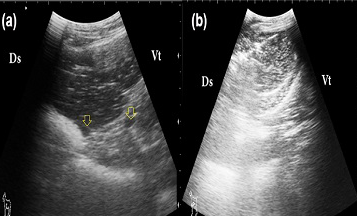

Ultrasonogram of liver in PT does

A: a good prognosis case; the liver appears more echogenic than the normal with visible hepatic vessels (arrows); B: a bad prognosis case: the liver appears more echogenic than the normal with invisible hepatic vessels; Ds: Dorsal; Vt: Ventral